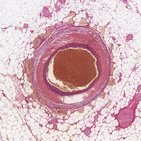

Histología de vasos sanguíneos

¡Este cuestionario personalizable incluye 31 estructuras en relación con 2 temas, incluyendo: Vasos sanguíneos y Arterias y venas!